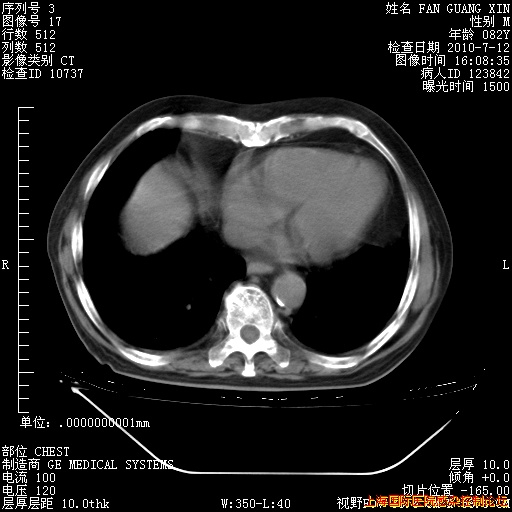

6月12日纵膈窗